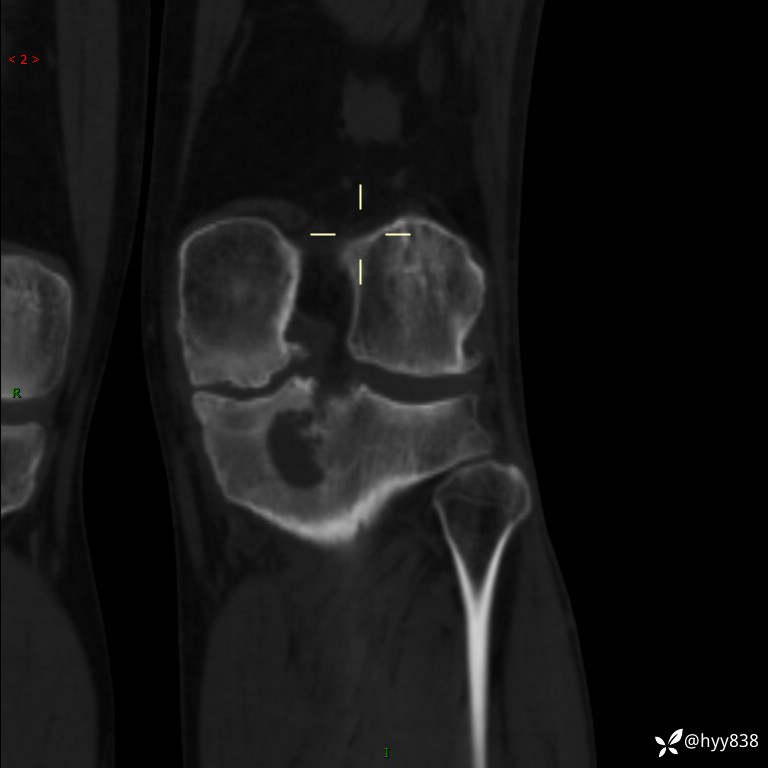

CT

干骺端溶骨性病变病灶周广泛水肿